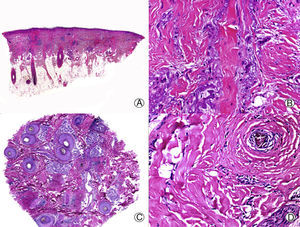

Desde el punto de vista histopatológico la PB se caracteriza por no presentar una dermatitis de la interfase, en contraste con el LPF o el LECC, pero no se han descrito características histopatológicas distintivas de PB33. Las lesiones tempranas presentan un infiltrado linfocitario perifolicular escaso o moderado, que predomina en la zona periinfundibular29. Las glándulas sebáceas resultan destruidas de forma temprana34. Con la evolución del cuadro aparece fibroplasia lamelar alrededor de los infundíbulos foliculares, que termina produciendo la destrucción completa de la unidad foliculosebácea, con aparición de tractos fibrosos en su lugar (fig. 3). El músculo erector del pelo se mantiene íntegro, y se pueden observar granulomas a cuerpo extraño, rodeando los tallos pilosos29. Con tinción para fibras elásticas la PB presenta fibras elásticas llamativamente engrosadas tanto en la dermis adventicial como reticular11, lo que ayuda al diagnóstico diferencial con otras ACP en fases avanzadas.

Pseudopelada de Brocq de larga evolución. A. Visión panorámica donde se observan columnas de fibrosis reemplazando a los folículos (HE x10). B. Detalle de la anterior mostrando fibrosis vertical entremezclada con elastosis actínica (HE x200). C. Corte transversal del mismo caso en el que se observan varias unidades foliculares (HE x20). D. A mayor aumento se aprecia fibroplasia concéntrica alrededor de restos foliculares (HE x200).